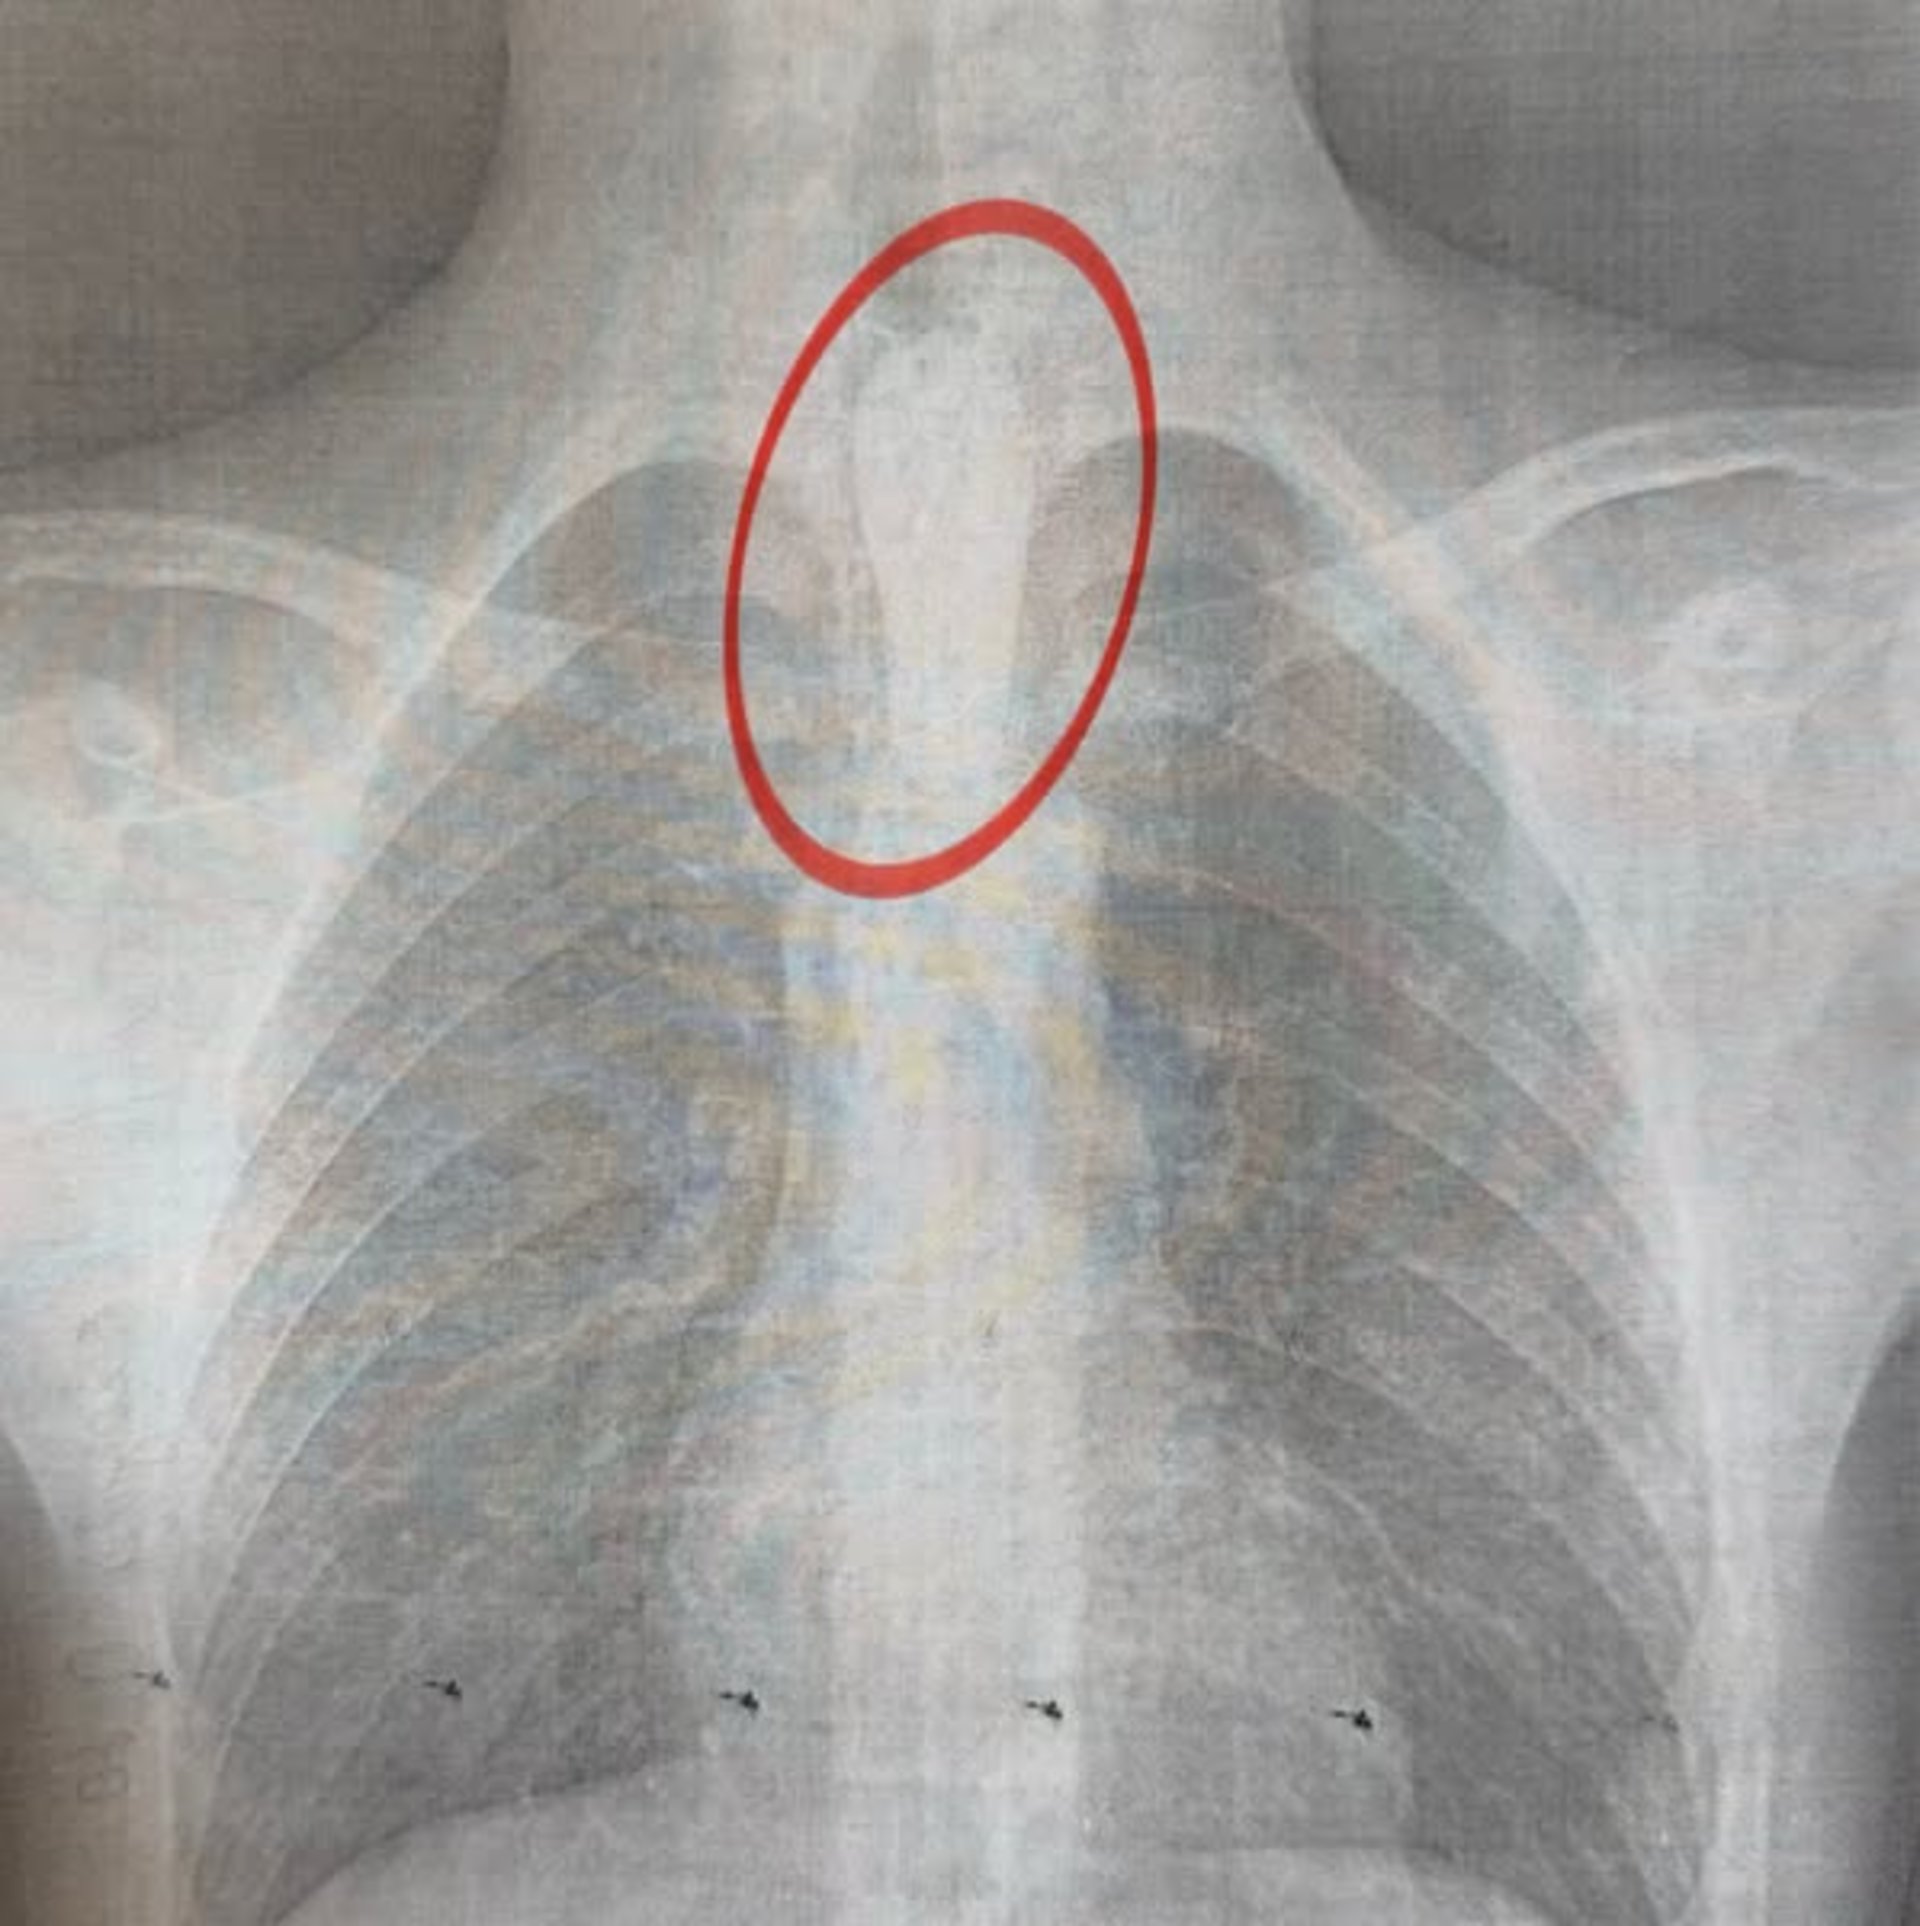

У Львові 14-річного хлопця з гострим порушенням ковтання та активною слинотечею госпіталізували до львівського Центру дитячої медицини «Охматдит». Під час вечері дитина проковтнула великий шматок шашлику, який застряг у стравоході.

Як повідомили у лікарні «Охмадит», до приймального відділення Центру дитячої медицини, лікарні "Охматдит" доставили 14-річного хлопця. Під час вечері він з'їв великий шматок шашлика, який застряг у стравоході. У дитини розпочалося порушення ковтання, активна слинотеча, вона не могла навіть ковтати власну слину, відчувала значний дискомфорт, страх і утруднене дихання.

"Стравохід має природні звуження: на рівні шиї, біля аорти та на вході до шлунка. У цьому випадку шматок м'яса зупинився на другому звуженні. Слина постійно виробляється, але не може пройти далі, що викликає сильну слинотечу, відчуття стороннього тіла за грудиною і страх. Дитина не могла нормально дихати", – розповів торакальний хірург нашого Центру Олександр Колодій.

Операцію провели вночі – о 2:00 хлопця терміново доправили до операційної, де команда фахівців виконала ригідну езофагоскопію. Втручання тривало близько години: великий шматок м’яса видаляли поетапно, щоб не пошкодити стінки стравоходу.

"Це дуже делікатна хірургічна робота. Необхідно діяти обережно, щоб не спричинити перфорацію стравоходу", – пояснює торакальний хірург Олександр Колодій.